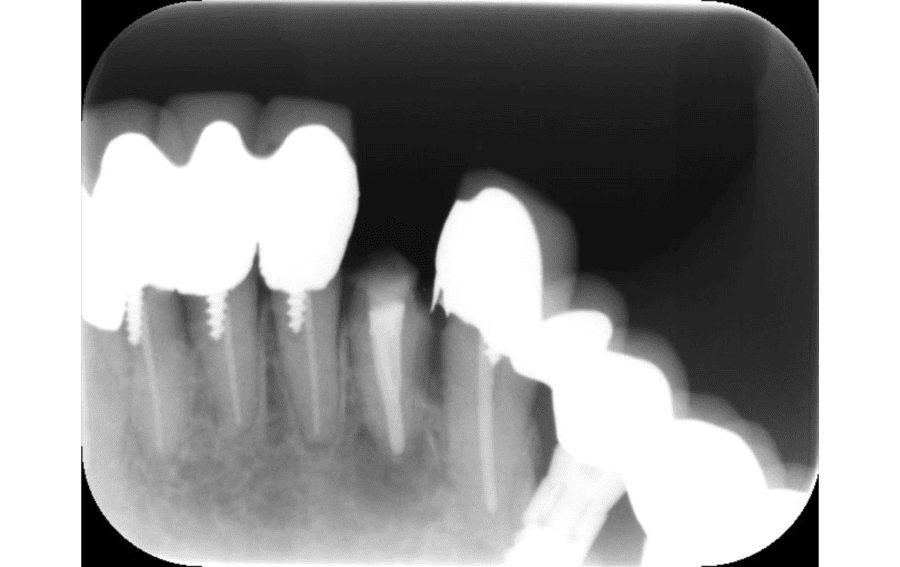

After

約4か月後(骨の回復が認められる)